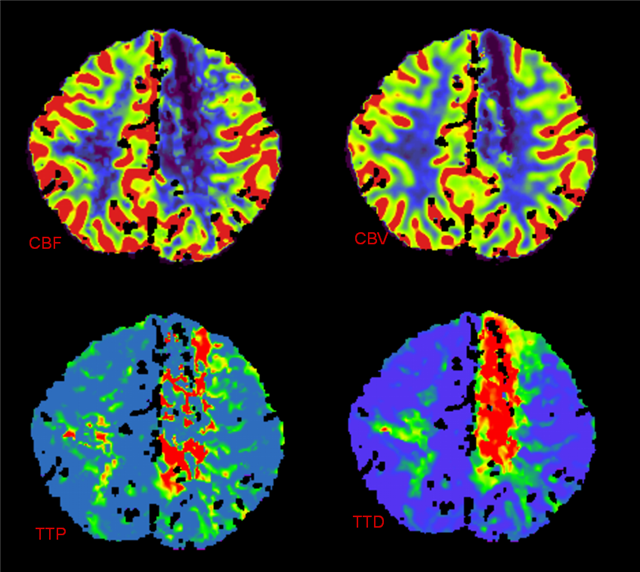

Clinical examination and MRI are often the first steps in an MLD diagnosis. MRI can be indicative of MLD but is not adequate as a confirming test. An ARSA-A enzyme level blood test with a confirming urinary sulfatide test is the best biochemical test for MLD. Urinary sulfatide is important to distinguish between MLD and pseudo-MLD blood results. Genomic sequencing may also confirm MLD, however, there are likely more mutations than the over 200 already known to cause MLD that are not yet ascribed to MLD that cause MLD so in those cases a biochemical test is still warranted.